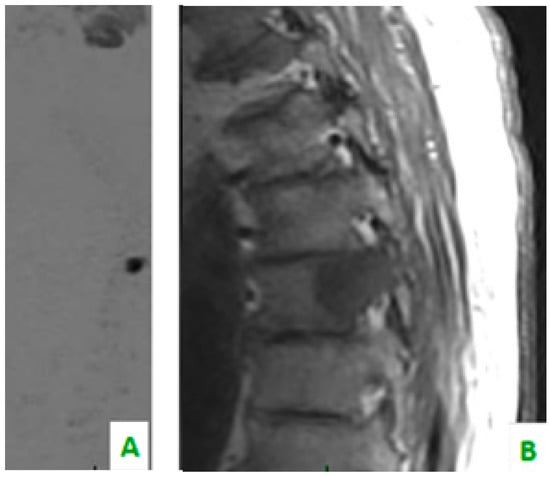

Figure 4. Focus on the red circles: (A) DIXON T2 weighted in the sagittal plane showing bone cervical metastasis (C5) (B) a low apparent diffusion coefficient (ADC) value in the same level, and (C) a restriction of diffusivity.